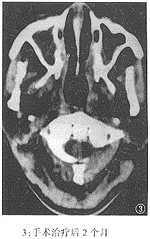

本组病例经随访观察3月~35月,平均17月(中位数15月)。除2例再粘连外,均取得了良好的通气效果。该组的CT显示:鼻腔粘连的部位多在鼻腔后份,表现为鼻甲与鼻中隔之间的空隙消失,为条索状致密阴影所填充,往往可在多个层面特别是在鼻腔的上部层面上可以观察到。治疗前后鼻甲与鼻中隔间的空隙恢复见图1、2、3。

附图 鼻腔粘连前后及手术治疗后的鼻腔CT表现

临床诊断鼻腔粘连不难,凡NPC放疗后有持续性鼻塞并伴流涕、嗅觉减退或丧失者,经鼻镜检查发现下、中鼻甲与鼻中隔相贴,用血管收缩剂不能分开,探针不能通过,粘连即可确诊。通过对经治疗的28例鼻腔粘连病例的鼻咽轴位CT的观察,发现鼻腔粘连的轴位CT有以下特点:鼻甲与鼻中隔之间的空隙消失,被条索状致密影代替;这条索状致密影往往可在多个层面特别是在鼻腔顶部的层面上观察到,而肿胀的鼻甲组织的密度较为均匀且以鼻腔下部为主,可以与因放疗引起的鼻腔粘膜肿胀及鼻腔分泌物相区别。与粘连前的CT片比较,也有助于CT上对该病的诊断。